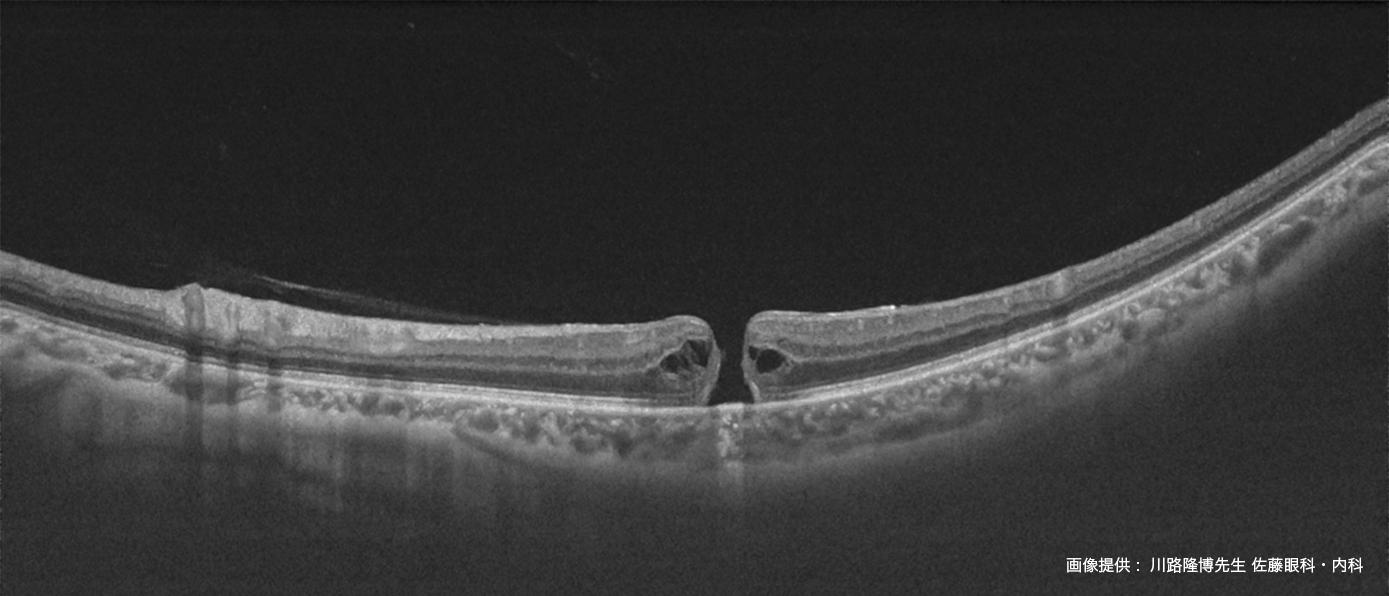

診断に有用な撮影機能を集約 - 白内障や硝子体混濁のある疾患眼に対しても鮮明なOCT 像を表示

DRI OCT Triton シリーズにトプコン独自のアルゴリズムOCT Angiography Ratio Analysis = OCTARA™を搭載したことで、

脈絡膜レベルの血流まで高感度、高侵達に画像化します¹。トプコン独自のアルゴリズムOCTARA は、

同じ断面で撮影された複数のOCT 画像から血管内の血流の様子を画像化する技術です。弱い信号変化でも高感度で画像化できるため、

毛細血管の観察など臨床に活用されています。